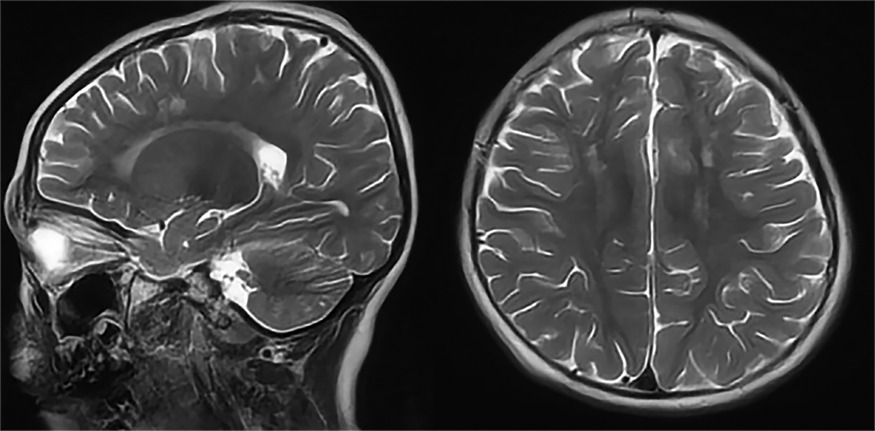

Multi-Organ MRI

MRI is another advanced imaging technique that provides detailed images of the body. It uses magnetic fields and radio waves to create detailed images of internal structures9. MRI machines contain large, powerful magnets that generate a strong magnetic field around the patient. When a patient is positioned inside the MRI machine, the magnetic field aligns the hydrogen atoms in the body in a specific direction.

The MRI machine then sends radio-frequency (RF) pulses, which temporarily alter the alignment of hydrogen atoms. When the RF pulses cease, the hydrogen atoms return to their original alignment, emitting energy as radio waves detected by the MRI scanner.

Due to their differing water contents, different tissues in the body have varying amounts of hydrogen atoms and thus release energy at different rates. The MRI scanner can differentiate between different tissue types and produce high-resolution cross-sectional images10.

With MRI, your radiologist can observe oedema11, inflammatory sites12,13, and other abnormalities, such as tumours and precancerous lesions14. An MRI scan is highly sensitive, fast, painless, and free of ionising radiation.